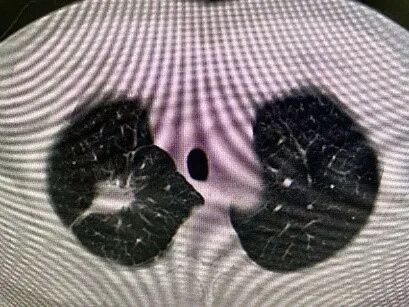

2021年1月,在病情趋于平稳、全身癌细胞控制良好的时候,肿瘤科针对杨先生肺内较大肿块进行了射频消融治疗。5个月后常规复查CT,发现做过消融治疗的肿块增大并且实性成分增多。医生心头一紧,难道是肿瘤再次发生进展了吗?

图片

治疗前dCJ帝国网站管理系统

射频消融后2个月dCJ帝国网站管理系统

射频消融后5个月dCJ帝国网站管理系统

病理报告:(肺穿)送检组织以纤维成分增生为主出血慢性炎伴大片坏死,另见少量肺组织。